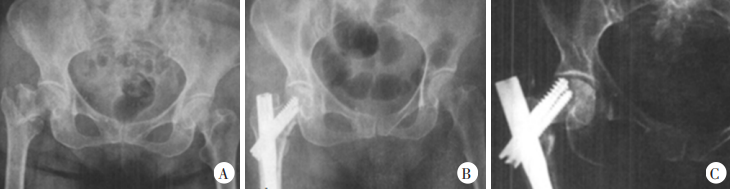

Рисунок 1. Пациентка, 65 лет, в результате дорожно-транспортного происшествия получила межвертельный перелом бедренной кости справа. А. На рентгенограмме переднезаднего отдела: межвертельный перелом бедренной кости, IV тип, нестабильный перелом. Б. Рентгенограмма переднезаднего отдела через 7 дней после операции. рентгенограмма показала, что перелом хорошо репонирован, внутренняя фиксация стабильна. C. На переднезадней рентгенограмме через 12 месяцев после операции выявлена варусная деформация тазика;